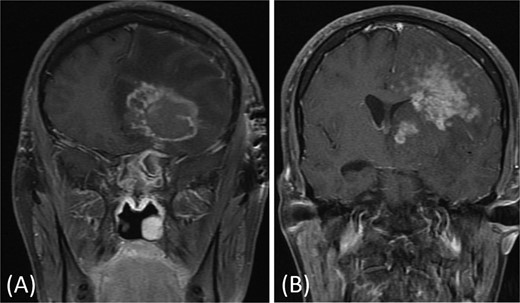

One year later, the patient presented to the emergency department with dizziness, vomiting, and headaches that had started 20 days prior. The CT scan and MRI showed orbital and intracranial invasion. Subsequently, the patient underwent FESS revision with an open craniotomy. The histopathological results revealed findings similar to the first presentation, so the patient was started on intravenous amphotericin B, voriconazole, and dexamethasone. The patient was stable postoperatively until 2 months when he began to deteriorate, and a brain MRI revealed a cerebral abscess (Fig. 4). The patient underwent an urgent open craniotomy with drainage and was shifted to the intensive care unit. However, his condition continued to worsen, and he passed away after 1 month.

Brain MRI showing right-sided cerebral abscess with midline shift to the left side.